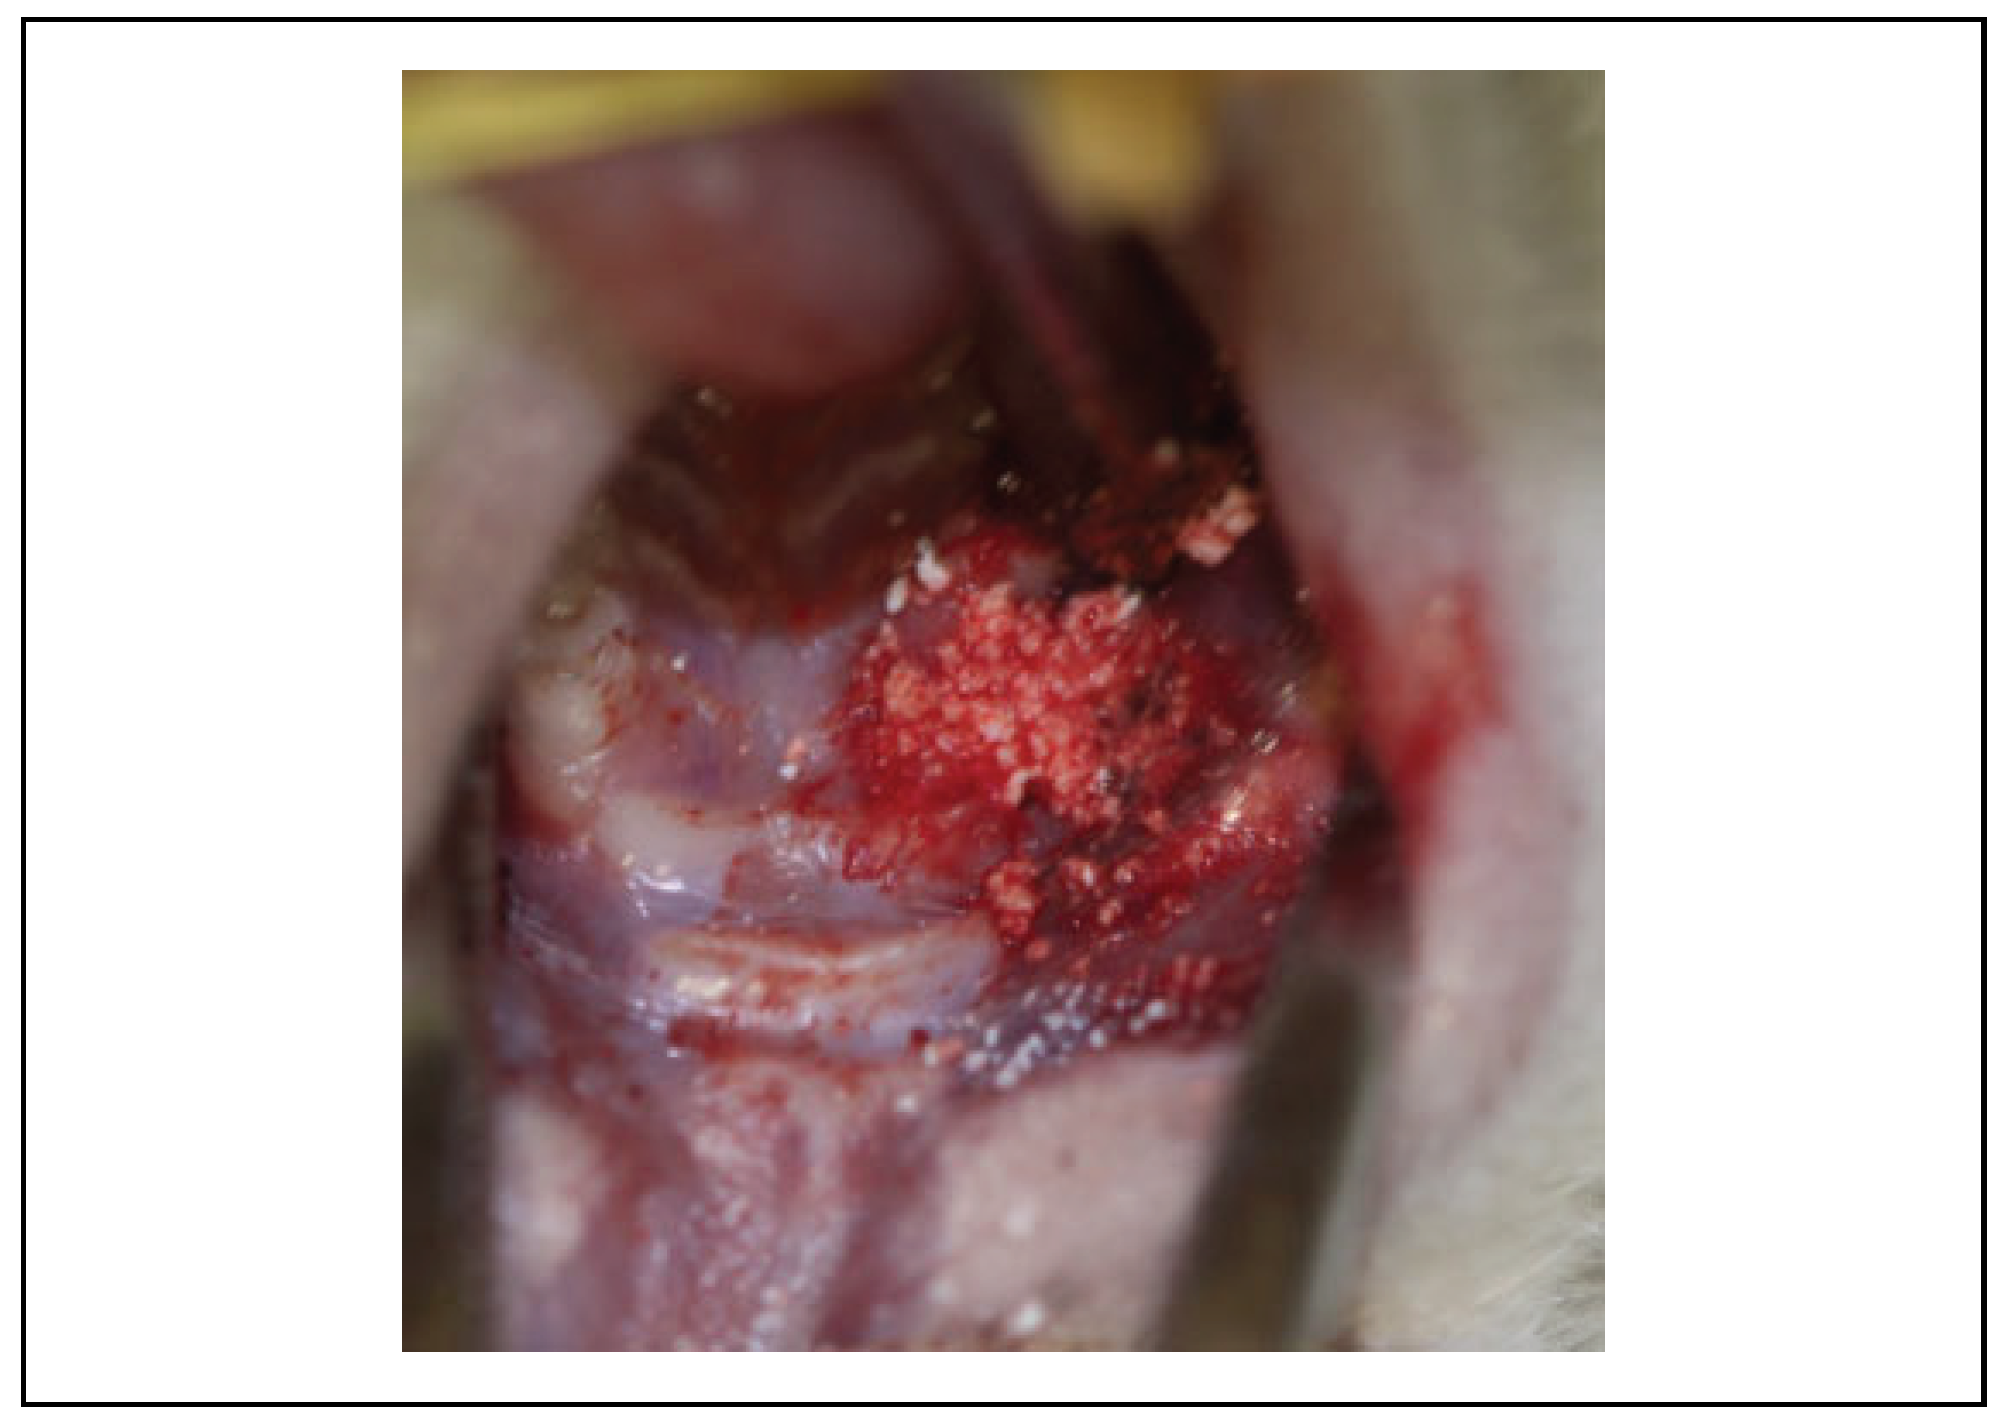

Clinical Evaluation

| Group | Necrotic Bone exposure | Normal soft tissue healing | Total of Animals |

|---|---|---|---|

| G1: Control Group | 06 | 0 | 6 |

| G2: Inorganic bovine bone graft (Lumina Bone®) | 0 | 6 | 6 |

| G3: b TCP(chronOS®) | 0 | 6 | 6 |